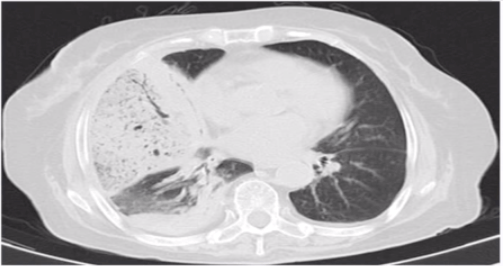

第四题:如下图所示 , 病变表现为右下肺云雾样浸润影 。

文章图片

第四题答案: 支原体肺炎 , 天气温暖时易发病 , 通常支气管受累 。